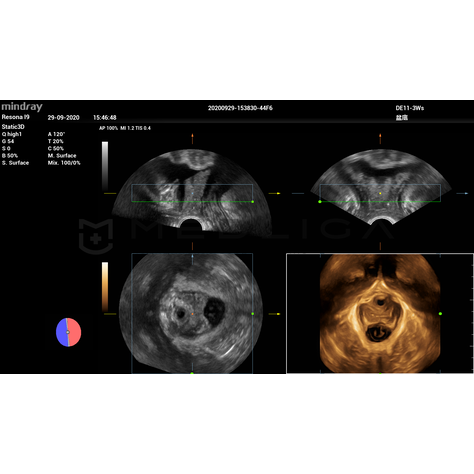

Программное обеспечение для автоматических измерений параметров и оценки функции мышц тазового дна.

Smart Pelvic - новое решение, позволяющее значительно упростить диагностическую процедуру и свести к минимуму время исследования функций мышц тазового дна. Благодаря чрезвычайно простому пользовательскому интерфейсу, программа генерирует стандартную систему координат и автоматически просчитывает все связанные измерения в течение нескольких секунд.